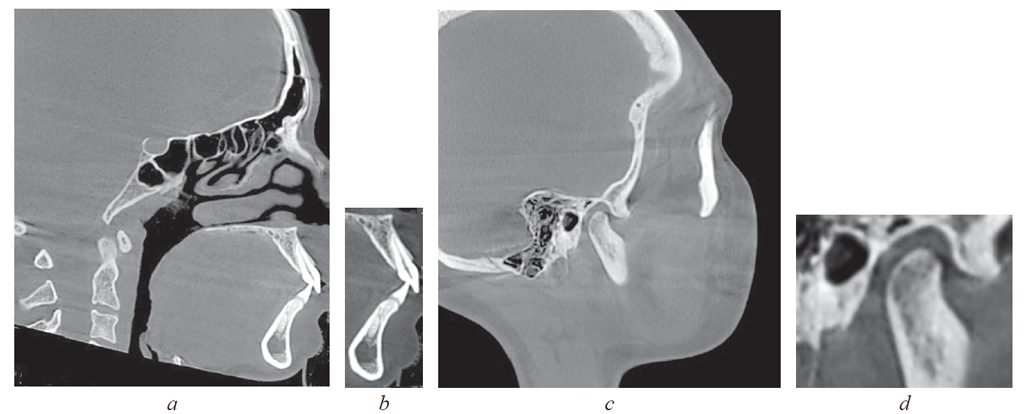

Во-вторых, выделяли фрагменты томограмм (рис. 2).

Рис. 2. Томограмма на уровне медиальных резцов (a); выделенный фрагмент зубочелюстных сегментов (b); томограмма на уровне сустава (c); выделенный фрагмент сустава (d)

Fig. 2. Tomogram at the level of medial incisors (a); the selected fragment of dentoalveolar segments (b); tomogram at the level of the joint (c); the selected fragment of the joint (d)